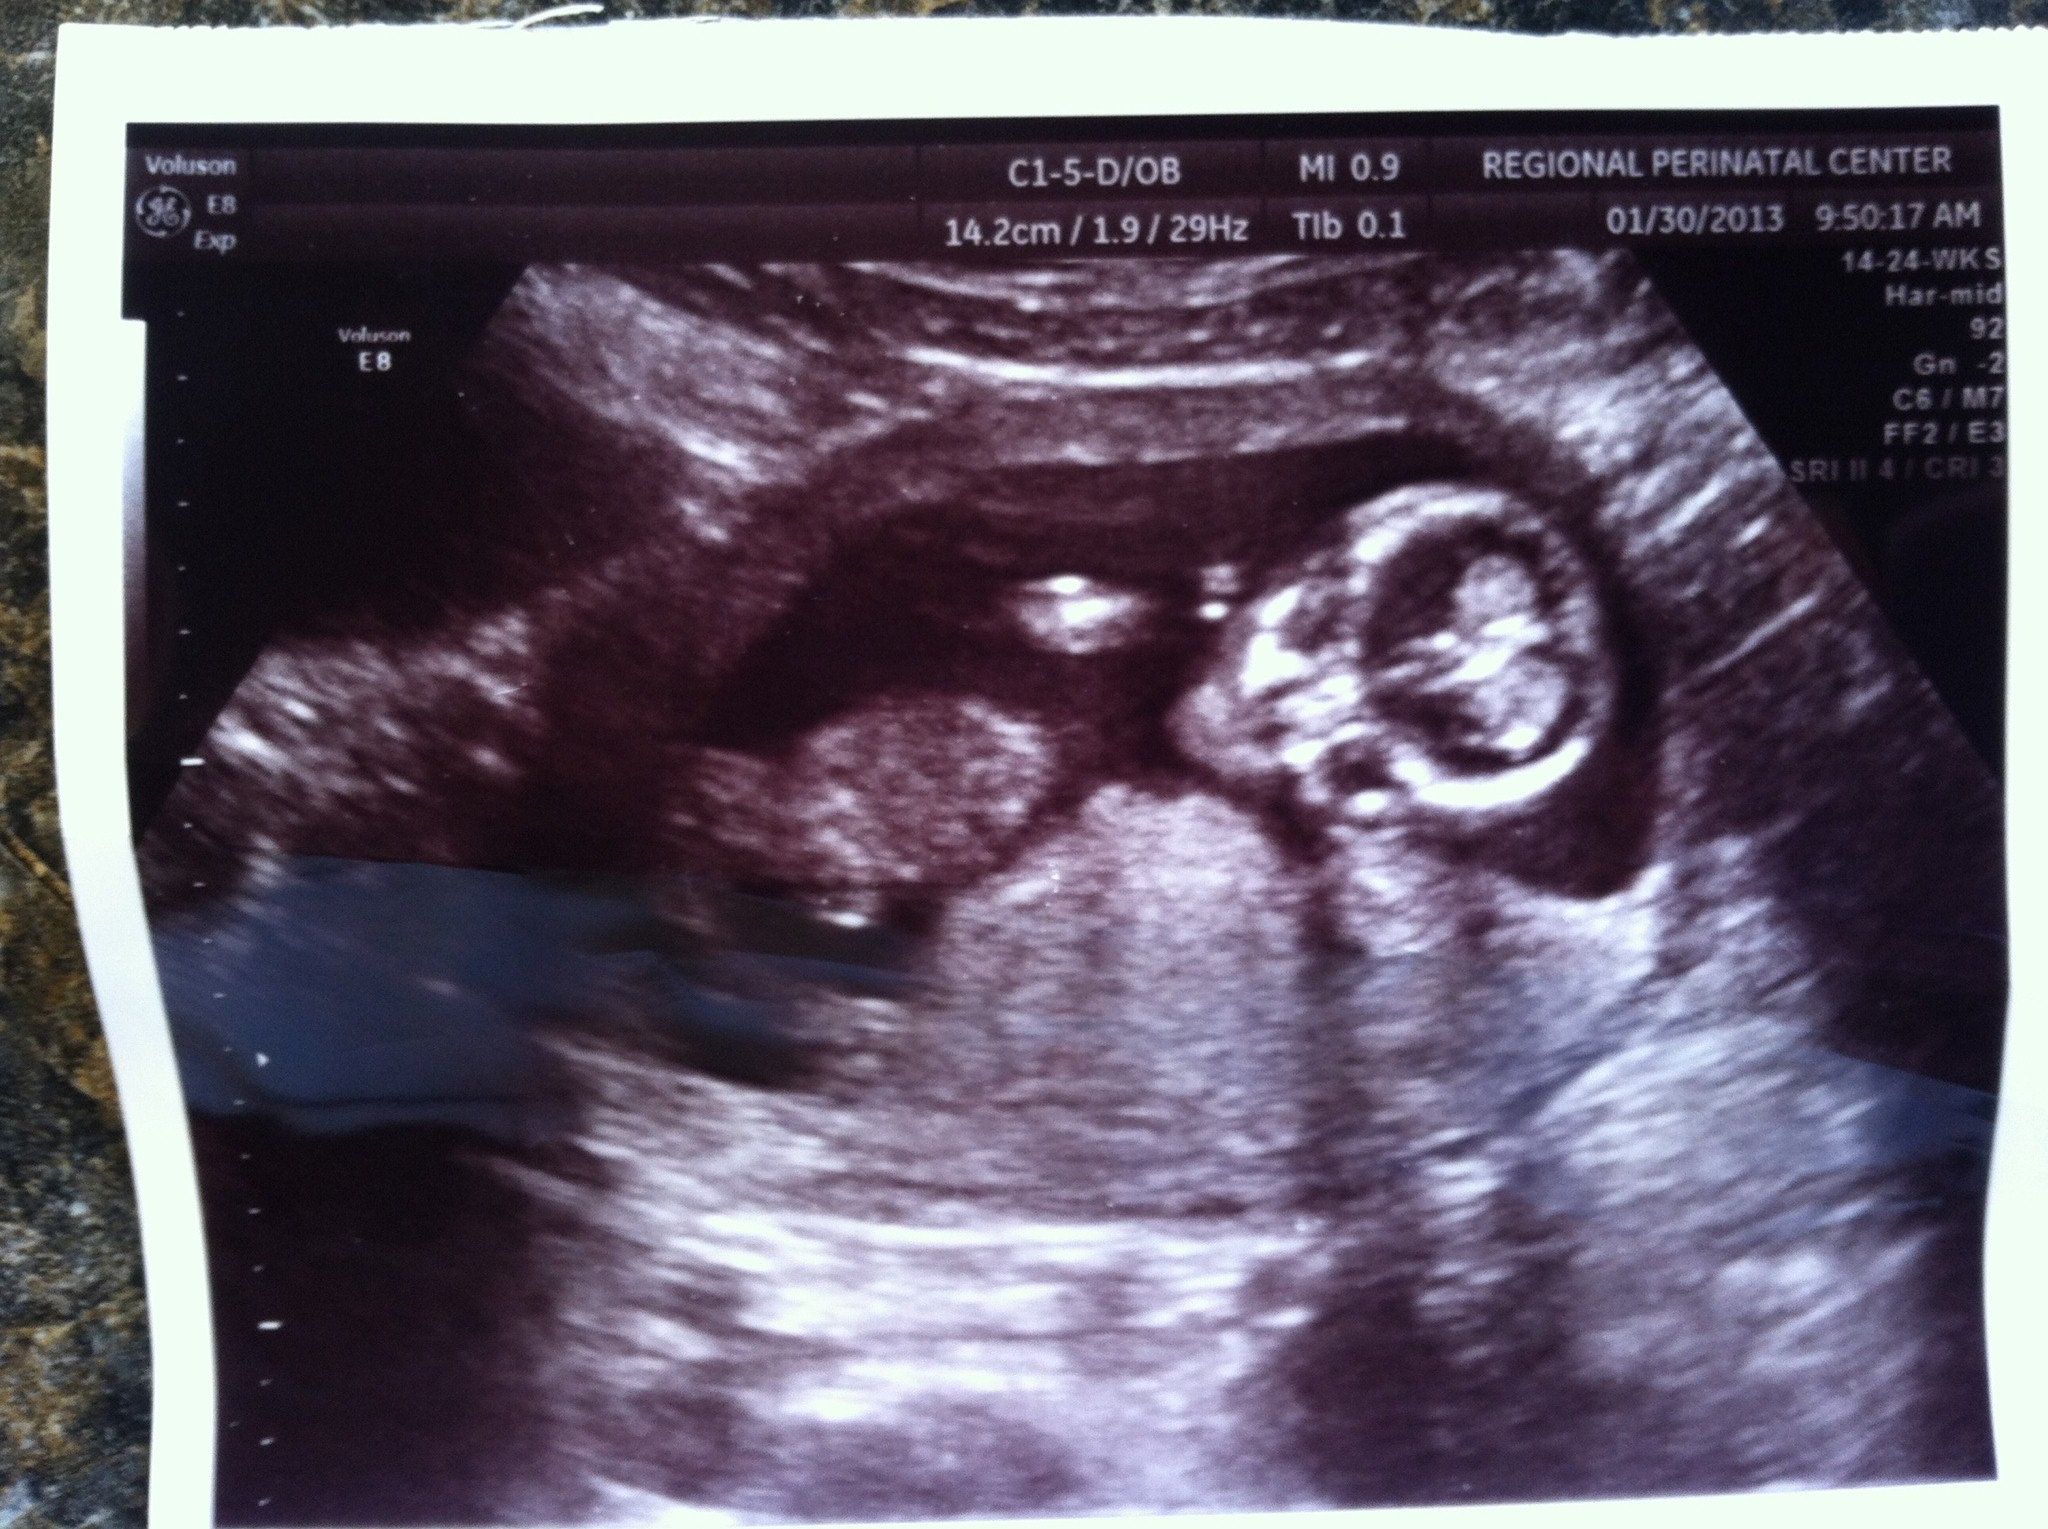

Well, the tech said if she had to give me ans. today she would say girl, but said there were a few views that said it could have been boy parts. Any gender guesses on this shot? Attachment 8503

No clues in this shot...did you get a potty shot?